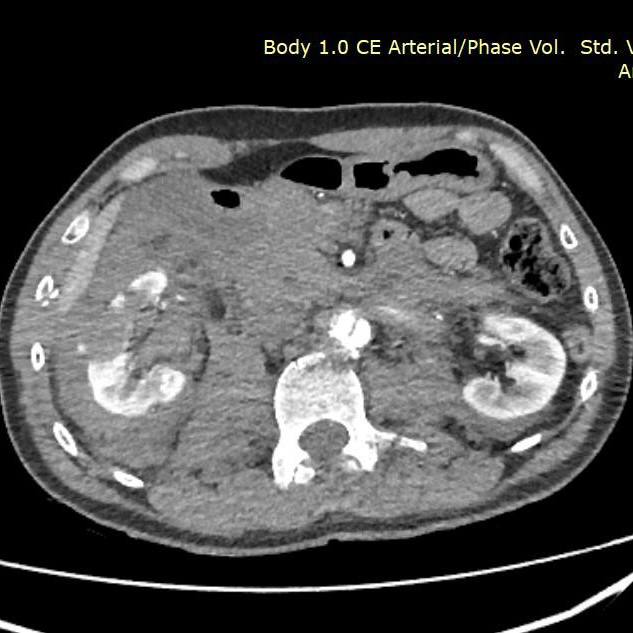

Петербургские врачи спасли пациента с тяжелой производственной травмой — госпитализация продолжалась 48 дней